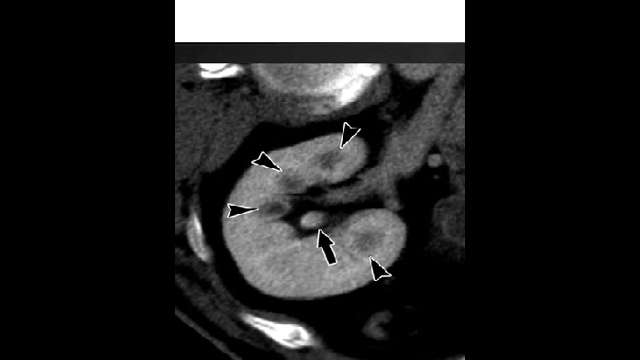

55-year-old male with post renal transplant with worsening renal function, HTN and gout attacks.